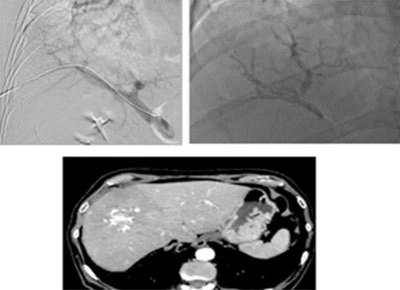

Un altro tipo di tumore del fegato, più raro, è il carcinoma fibrolamellare. Questa forma di cancro è generalmente diagnosticata in pazienti giovani e, rispetto al carcinoma epatocellulare, tende ad essere meno invasiva e a crescere in modo più ben delimitato. Una caratteristica distintiva del carcinoma fibrolamellare è la presenza di una lesione fibrotica centrale, visibile attraverso tecniche di diagnostica per immagini come la risonanza magnetica o la tomografia computerizzata (TC).

Sebbene si tratti di una forma rara, il carcinoma fibrolamellare viene trattato nella maggior parte dei casi come il carcinoma epatocellulare, con approcci terapeutici che possono includere chirurgia, trapianto di fegato, chemioembolizzazione o terapia sistemica.